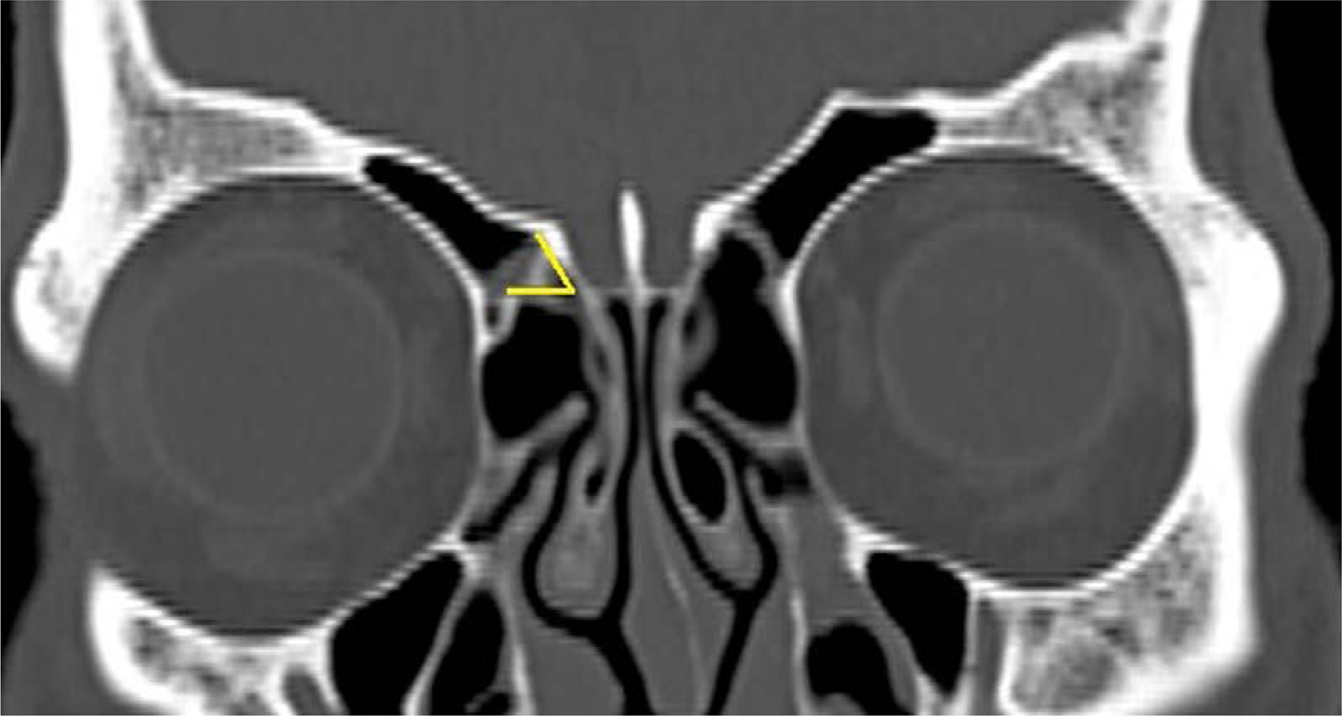

Figure 4

Gera classification9 was assessed by measuring at the angle formed by the lateral lamella of the cribriform plate and the continuation of the horizontal plane passing through the cribriform plate in the CT coronal plane and classified as Class I, II and III.